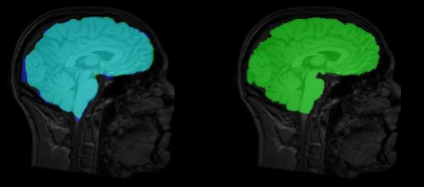

Skull stripping

Brain extraction is the very first step of any brain imaging pipeline

Recently highly generalizable methods have been developed but there is room for more improvement.

While several algorithms have provided fast and accurate results for several modalities,

recent advancements in Deep Learning has shown improvement in speed, accuracy and generalizability.

Supervised Deep learning approaches can be used to provide a highly accurate method, while unsupervised methods can provide a more general segmentation.

The main focus points of related research include generalizability, speed, efficiency and accuracy